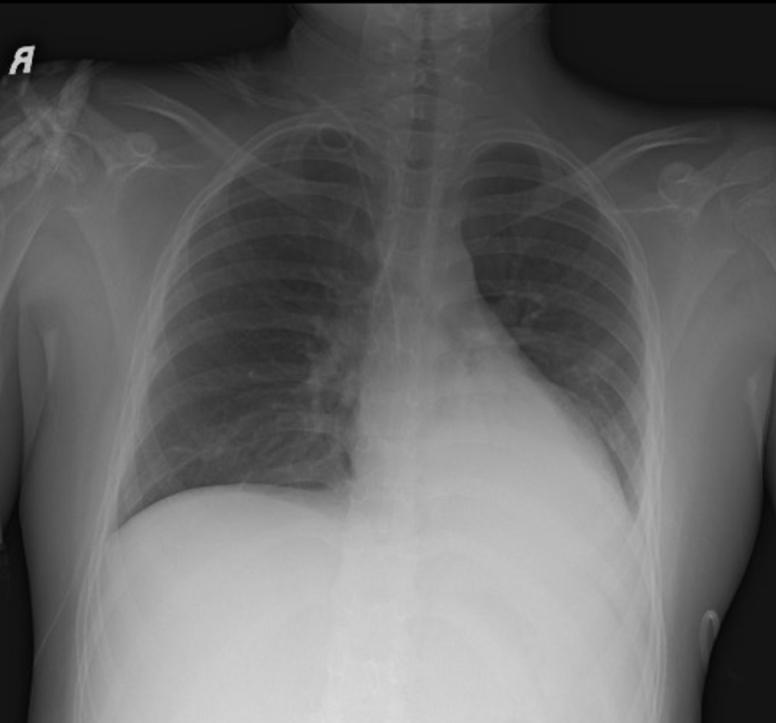

A young child presented with severe ventricular dysfunction and troponin leak in the setting of coronavirus disease-2019. He developed intermittent, self-resolving, and hemodynamically insignificant episodes of complete heart block that were diagnosed on telemetry and managed conservatively. This report is the first description of coronavirus disease-2019-induced transient complete heart block in a child. ().

一名幼儿在2019冠状病毒病的情况下出现严重心室功能障碍和肌钙蛋白泄漏。他出现了间歇性、自行缓解且血流动力学无显著意义的完全性心脏传导阻滞发作,通过遥测诊断并采取保守治疗。本报告首次描述了2019冠状病毒病诱发儿童短暂性完全性心脏传导阻滞的情况。